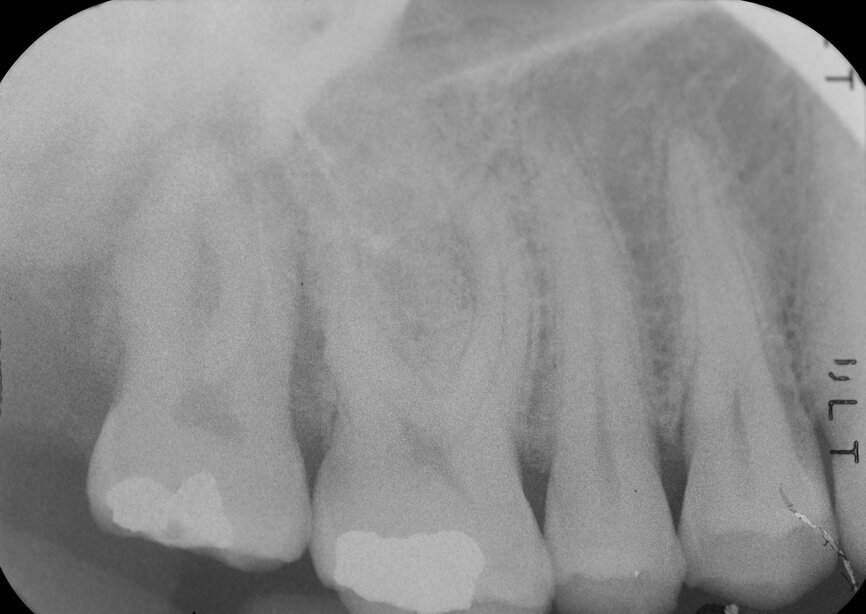

Fig. 3: Pre-op periapical radiograph.

A 47-year-old male patient in a good medical condition and a non-smoker was referred to our dental practice for endodontic retreatment of the right maxillary second molar. The dental history revealed that the tooth had been endodontically treated three months before because of acute pulpitis. After the treatment, the patient complained of pain on chewing. Antibiotics and a non-steroidal anti-inflammatory drug were prescribed, but the pain remained. After a month, a sinus tract appeared. The tooth was retreated in another practice without success. The clinical inspection revealed the presence of a sinus tract near the apical region of tooth #17. The tooth had been prepared for a full crown, but was without even a temporary crown, and the access cavity had been closed with temporary filling material. Cracks were evident on the buccal and mesial surfaces. Periodontal probing showed a deep pocket (> 12 mm) on the distal aspect of the root trunk (Figs. 1 & 2). The periapical radiograph showed a radiolucency between the roots of the second and third molars. The radiographic appearance of the endodontic treatment was good, without clear evidence of periapical radiolucencies (Fig. 3). A perforation of the pulp chamber floor was suspected. A CBCT scan was performed (Figs. 4–7), and it confirmed the suspicion of perforation, along with the presence of a large periradicular radiolucency and an unfavourable root shape.